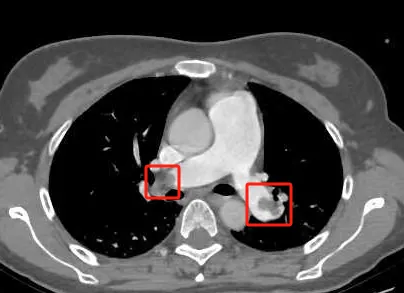

影像显示血管栓塞

(网络图片)